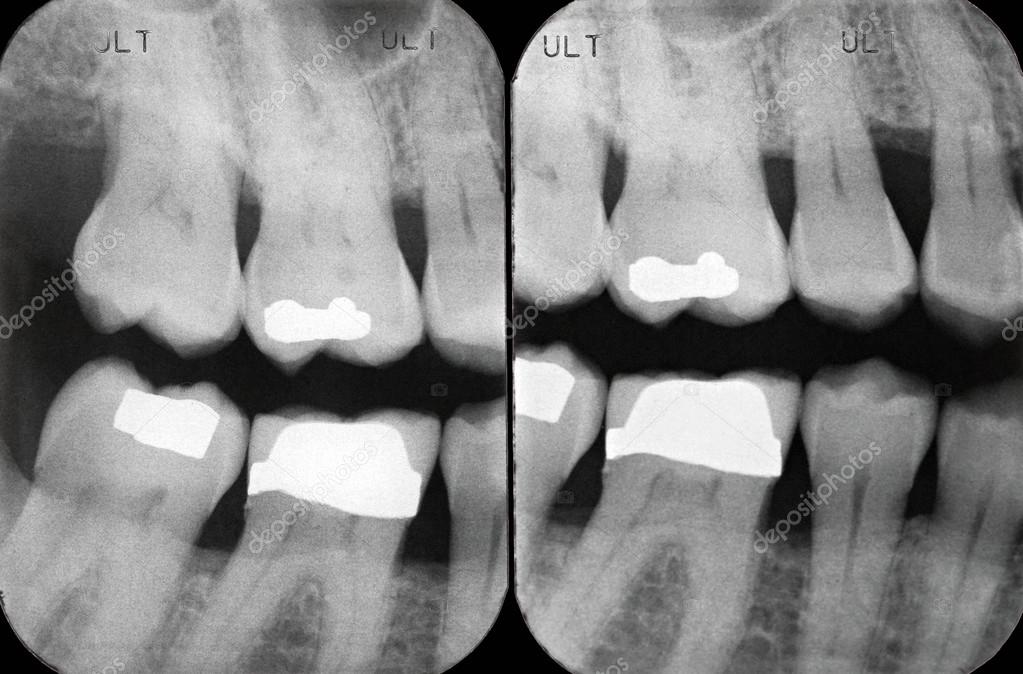

From www.dreamstime.com

Right Upper Periodontal Xrays Stock Image Image of black, dentin Periodontal X Ray The optimal projections for periodontal diagnosis in the posterior teeth are bitewing radiographs if. an opg provides us a complete bilateral view of dentition, maxilla, mandible and temporomandibular joint (tmj). it is generally widely accepted that radiographs supplement clinical examination in establishing the diagnosis and guiding. the use of the periodontal probe in the periodontal pockets around. Periodontal X Ray.